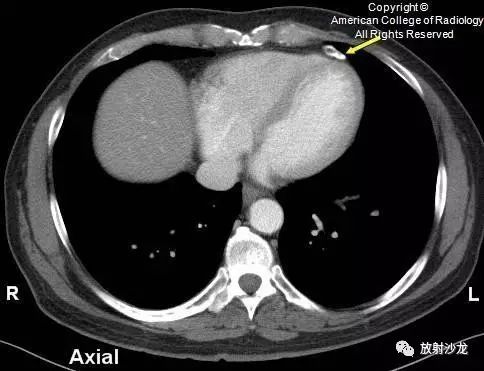

下图为另一患者的CT图像,显示左前外侧心包腔内慢性心包脂肪坏死病灶出现边缘环状钙化,与腹腔内网膜附属物的钙化表现相似。